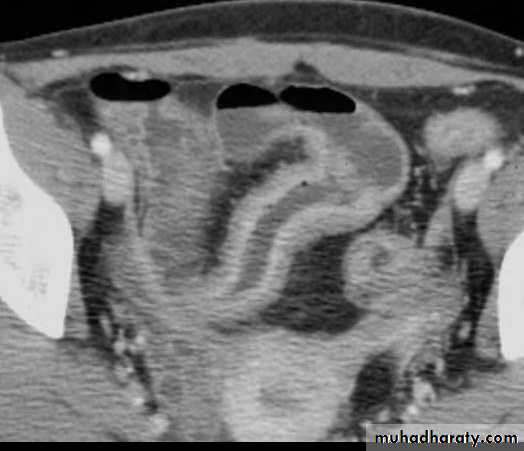

c. Due to bowel wall thickening, the folds may be thickened, distorted or disappear & the loops may be separated in severe wall thickening. With inflammatory mass, greater displacement of loops is seen.Mucosal fold thickening, ulceration, nodularity, asymmetric bowel wall

involvement, regions of narrowing, and separation of small bowel loops are present.d. Fistulae to the other loops of SB, colon, bladder or vagina.